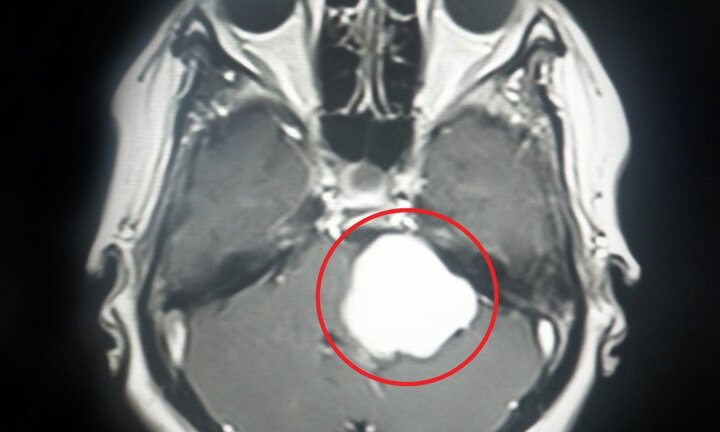

Bệnh viện Xuyên Á (TP.HCM) vừa phẫu thuật thành công ca tách khối u màng não to như quả bóng bàn ra khỏi mạch máu thần kinh của nam bệnh nhân.